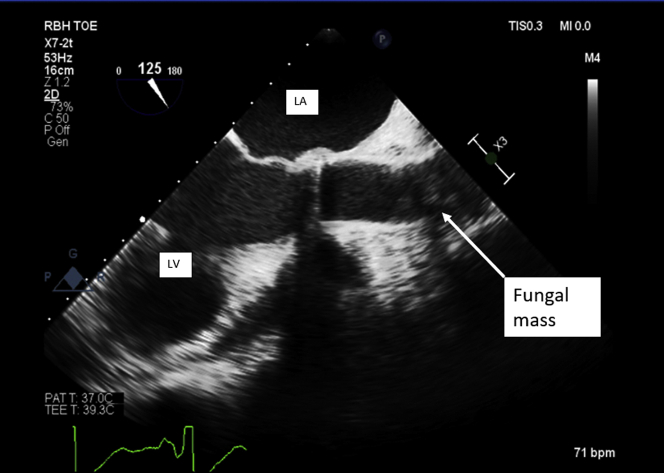

A transesophageal echocardiogram performed pre-operatively confirmed a normally functioning prosthetic valve with shadowing in ascending aorta, previously unseen on TTE (Figure 3, Videos 1 and 2). These images correlated with computed tomography findings, which identified a large, irregular filling defect in the aortic root (Figures 4A to 4D).

Figure 3.

Transesophageal Echocardiogram of Left Ventricular Outflow

Echo-dense mass partially visualized in the ascending aorta, likely at the suture line from a previous operation. bpm = beats/min; LA = left atrium; LV = left ventricle; MI = mechanical index; PAT = patient; RBH = Royal Brompton Hospital; TOE = transoesophageal echocardiogram; 2D = 2-dimensional.

Transesophageal Echocardiogram of Left Ventricular Outflow. Mobile mechanical aortic prosthesis discs with a shadow in the distal ascending aorta.

Transesophageal Echocardiogram of Ascending Aorta. Large mass obstructing the ascending aorta lumen. Confirmed post-operatively as a fungating mass.